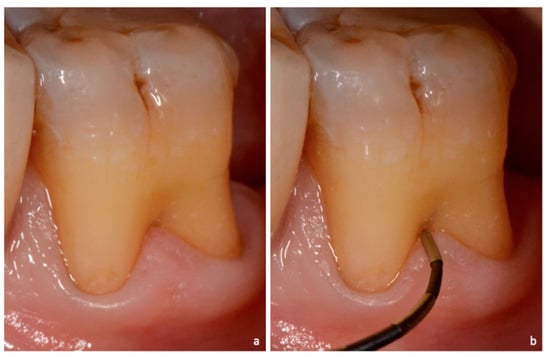

Figure 7. Exposed furcation lesion—Class I (EI): (a) First mandibular molar; (b) Buccal furcation lesion with horizontal attachment loss of 1 mm.

Class I: incipient lesion. There is slightly horizontal attachment loss in the furcation area. The examiner probe penetrates two millimeters or less from the entrance of furcation (Figure 2, Figure 3 and Figure 7).